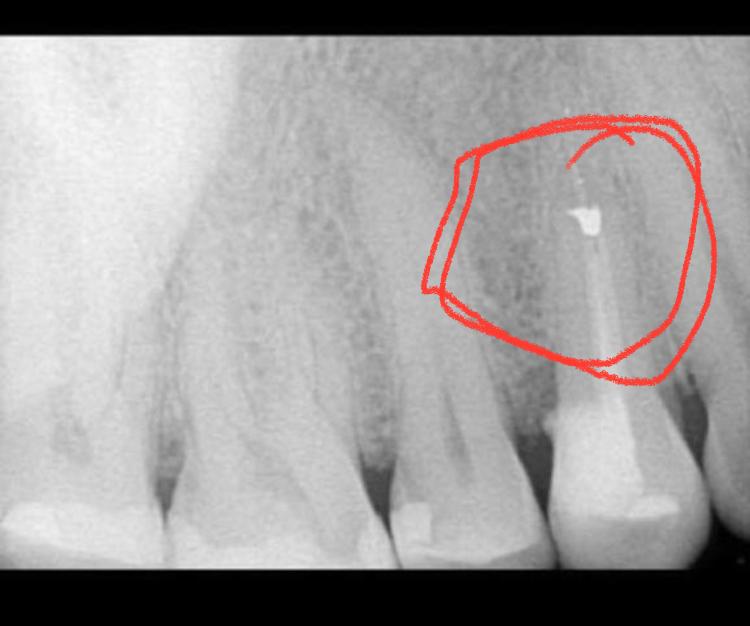

Örnek 2 ve 3 :

Bu vantuzlardan ikisinin altında çürük vardı, bu yüzden diş hekimi yaptığı şey hakkında biraz daha iyi hissetti. Ama birinin altında küçük bir parça amalgam vardı. Kucağıma düştü ve onu aldık. “Bu kadar küçük bir parçanın çok fazla soruna neden olabileceğini mi söylüyorsun?” diye sordu bana. Evet kesinlikle! Hatta ondan daha küçük parçalar bile sorundu!

Kardeşim hayatında birçok metale maruz kaldı. Karışık bir metal zehirlenmesi yaşadı. Erken başlayan alzheimer hastalığı gibi görünen bir hastalıktan acı çekti. Şelatlama konusunda herhangi bir ilerleme kaydetmediği için dişçiye geri döndük ve herhangi bir şeyi gözden kaçırıp atlamadığını görmek için panoramik bir fotoğraf istedik. Amalgam kalıp kalmadığı için özel röntgenlere ihtiyacınız olduğunu biliyorum. Kardeşimin dişinin röntgeninde küçük bir hilal şekli vardı, bu diş hekiminin gözden kaçırdığı küçük bir amalgamdı. Zavallı erkek kardeşim ‘’o küçük amalgam parçası” ile yıllarca şelasyon yaptı ve benim gibi şiddetli semptomları olmamasına rağmen, hiçbir zaman iyileşmedi. Birkaç ay önce ilerleyen demanstan öldü. Bana gelince, kronlarımı temizledikten sonra, olaysız şelat yapabildim ve o zamandan beri sağlığımı iyileştirdim.

Şimdi, herhangi bir ilerleme kaydetmeyen ve şelatör dozunu artıramayan insanlar gördüğümde, aklıma ilk gelen şey dişlerinde bir “küçük bir amalgam parçası ” kalmasıdır.

Pek çok diş hekimi, amalgamın son damlasını çıkarmanın ne kadar önemli olduğunun farkında değildir.

Diş hekimleri gerçek dişin mümkün olduğunca çoğunu sağlam bırakacak şekilde eğitildi. En iyi bütünsel diş hekimi bile bir tacı geri takmadan önce arkasında küçük bir cıva lekesi bırakmanın sorun olmadığını düşünebilir.

Herhangi bir tür şelatör alacaksanız, dişleriniz üzerinde mükemmel bir iş çıkarmanız gerekir. Çalışmanın ısırık röntgenlerini alın ve ikinci bir görüş alın. Diş hekiminin bir taç takmasına izin vermeden önce herhangi bir dişin röntgenini çekin. Kimsenin sözüne güvenmeyin. Söz konusu olan sizin hayatınızdır, bu yüzden akıllı ve tetikte olun.

Eskiden sökülmüş bir dişte veya diş etinde, çene kemiğinde sızıntı yapmış amalgam kalıntısı tespiti için : Üç boyutlu 768’li matrix ile dental-CT çekilmesi gerekir.

Çene bölgesinin dikkatli bir teşhis incelemesi kritiktir: Amalgam çıkarılmış hastalarda bile, kronların veya dolguların altında, köklerin ucunda, çene kemiğinde, paranazal sinüslerde ve ayrıca oral mukozal dokularda kalıntı izleri sıklıkla bulunabilir. Bunlar standart X-ışını görüntülerinde görülemez. Bunları görselleştirmek, özel DVT1 tabanlı diyagnostikler veya nadir görülen 768 Matrix ile çok yüksek çözünürlüklü CT2 taramaları gerektirir.